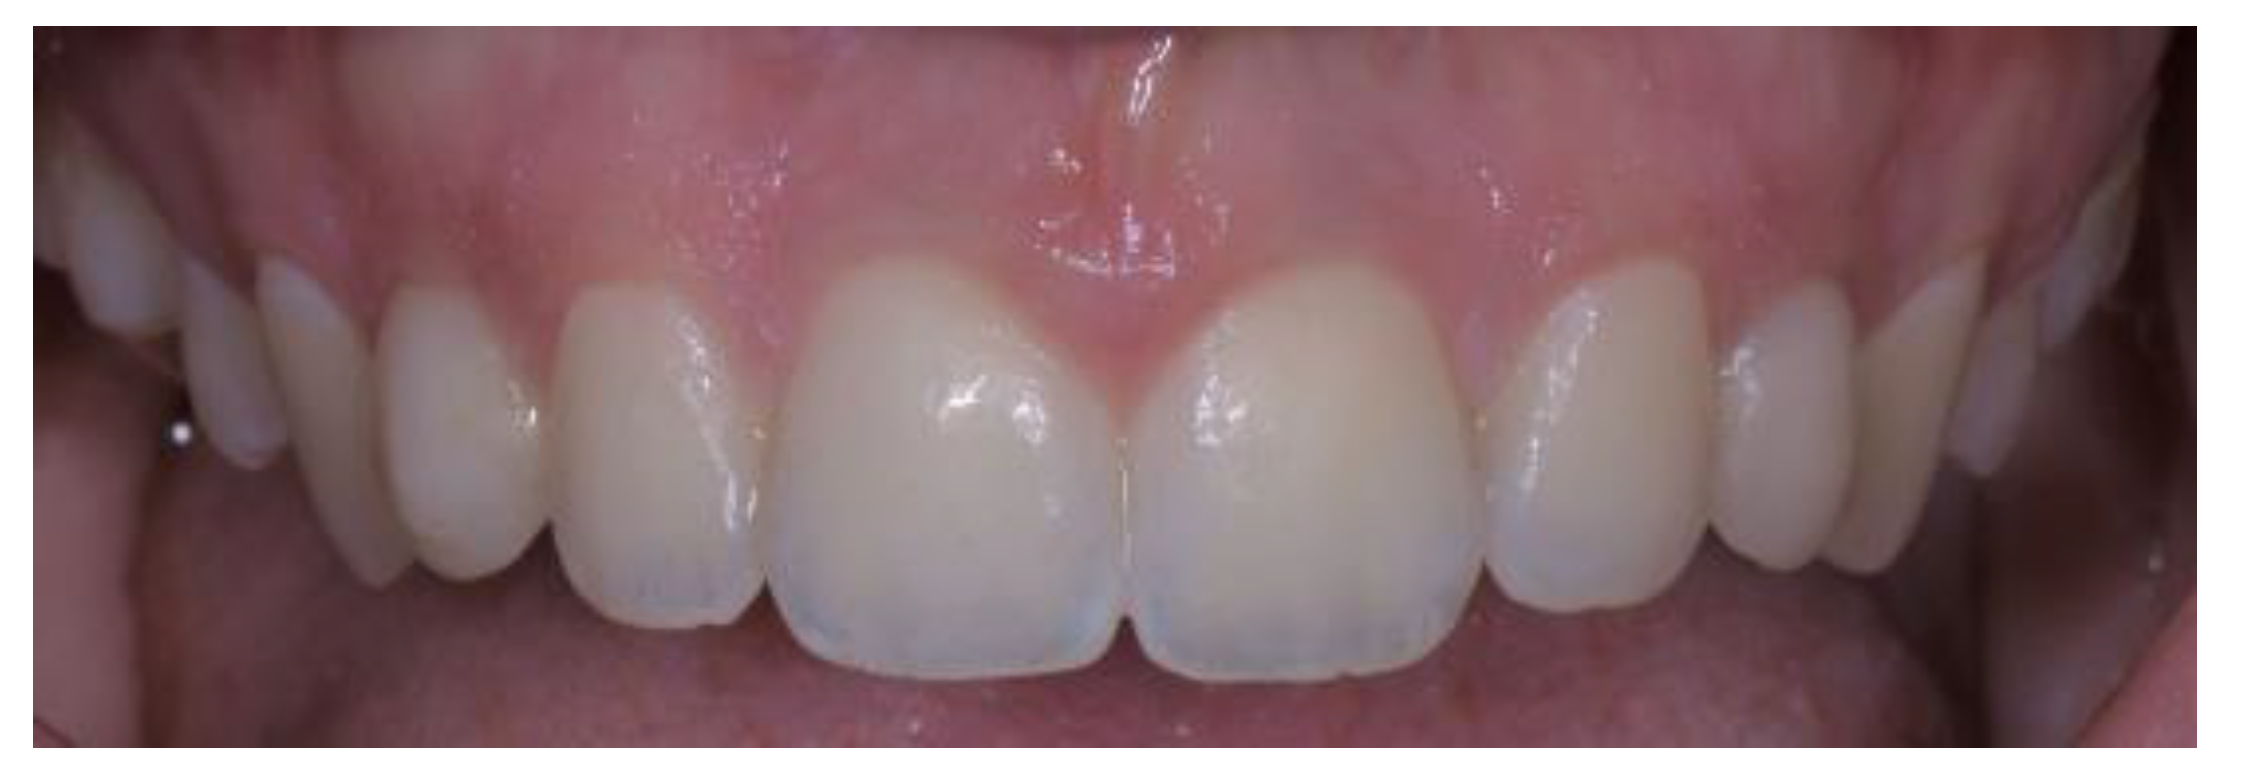

- Case 1:

- Case 2:

- Case 3:

- Case 4:

- Case 5: